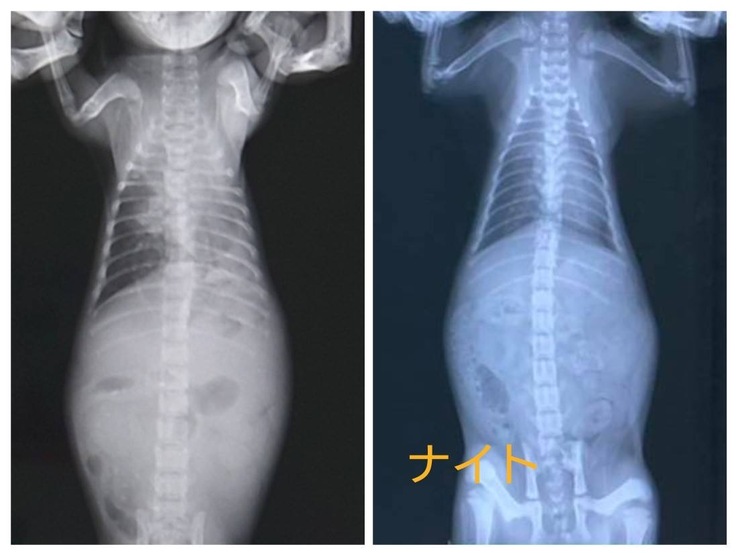

退院時(左)と現在(右)の肺のレントゲンを比べてみました。2匹ともまだ少しモヤはかかっていますが、だいぶ綺麗になりました。

ナイトの漏斗胸ですが、マッサージの甲斐もありほとんどわからないぐらいまで治りました。ただ一度歪んだ(凹んだ)骨は凹みがなくなっても少し外側に反ってしまっています。今のところ特に日常生活には問題はありません。今後もしっかり観察していこうと思います。